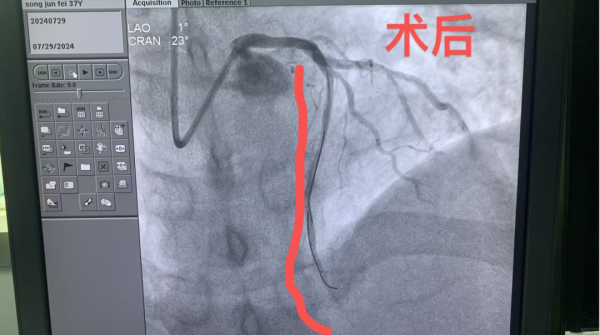

1、39岁男性,前降支闭塞,行血栓抽吸+冠脉内溶栓。

2、71岁男性,右冠闭塞,行药物球囊扩张成形术。

3、69岁男性,双支病变,行介入治疗。